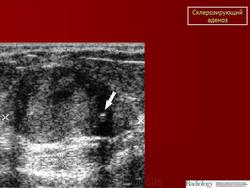

Склерозирующий аденоз. Ср, 25/01/2012 - 22:52 #1 Катенёв Валенти... Не на сайте Был на сайте: 7 лет 3 месяцев назад Зарегистрирован: 22.03.2008 - 22:15 Публикации: 54876 Склерозирующий аденоз.Приложения:

Склерозирующий аденоз.